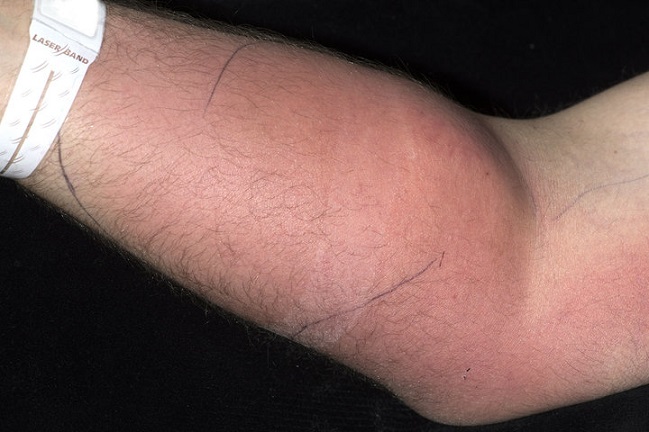

Su brazo estaba evidentemente inflamado, pues se inyectaba al menos una vez al mes durante los últimos 18 meses.

Cuando un médico se dio cuenta de la situación y logró que el hombre confesara el ignorante método, terminaron hospitalizándolo y sometiéndolo a una terapia anti microbios.

Luego de la limpieza, esta vez realmente conducida por expertos, su dolor de espalda se redujo.